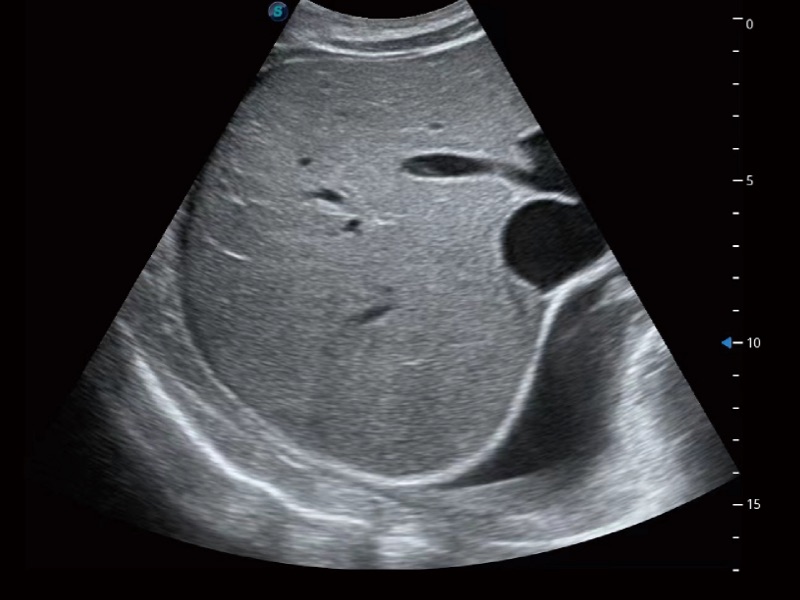

超声检查得益于实时性、经济性、便捷性,目前广泛的应用于临床工作中,超声检查设备已成为帮助临床医生轻松地完成诊断工作的好伙伴。P20 Plus集成了一整套包含了腹部、心血管、小器官、妇产科等全面临床应用功能,轻松应对各种临床问题。

• 腹部应用